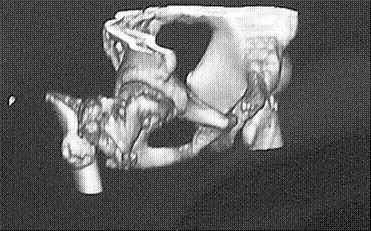

Уважаемые коллеги! Нужен совет.Больной Х., 21 год, ДЗ: ложный сустав вертельной области правого бедра.

Травма 8 мес. назад, ДТП, получил закрытый межвертельный перелом правого бедра. Лечился в городской больнице одного из городов-спутников г. Караганды скелетным вытяжением в течение 3 недель, затем кокситной гипсовой повязкой 2 мес. В настоящее время имеется укорочение конечности на 7 см, умеренная боль в вертельной области; ходит без костылей, полностью нагружая больную конечность, при нагрузке отмечается смещение дистального отломка проксимально примерно на 1,0 см.; объем движений в коленном суставе сохранен; при пальпации отломков боли нет, умеренная патологическая подвижность. Планируем внеочаговый остеосинтез спице-стержневым аппаратом, дистракция до восстановления длины бедра, вторым этапом остеосинтез стержнем Гамма. Есть надежда, что на дистракции пойдет сращение и у больного хватит терпения завершить лечение в аппарате.

Если судить по снимкам, то укорочение кажеться не критическим, но обьективно и на 3D - укорочение на 6-7 см.